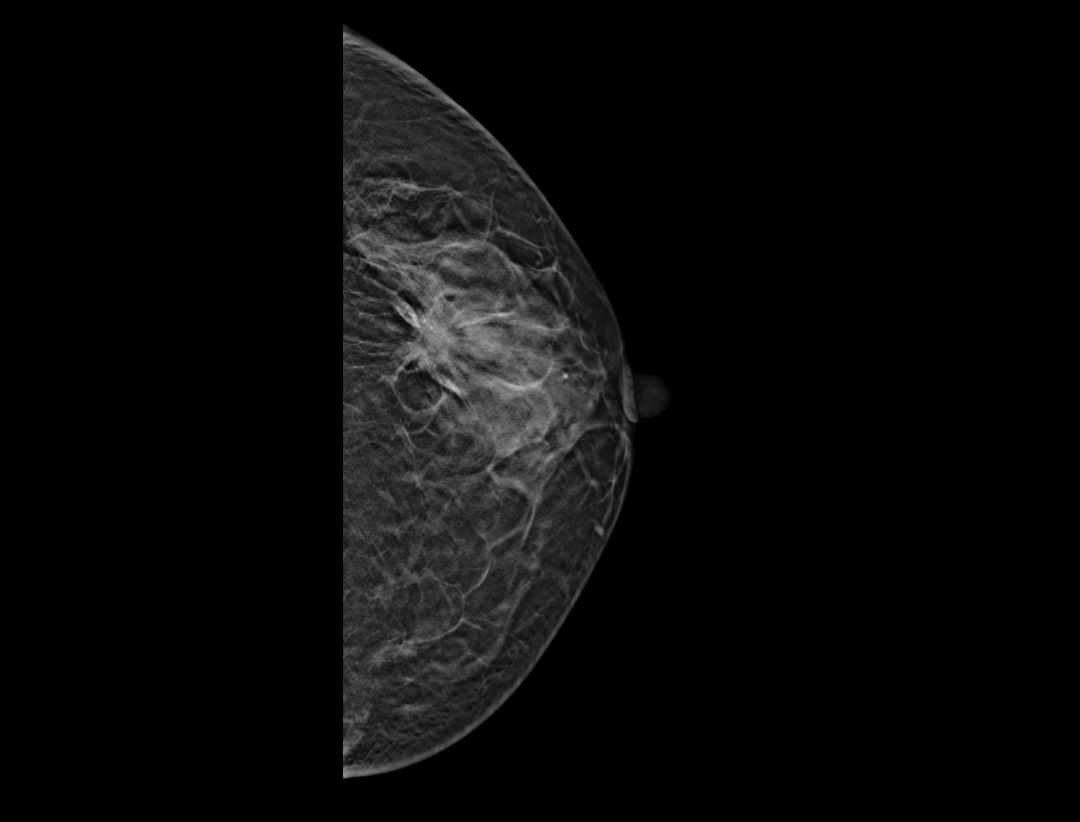

Adaptacyjne dostosowanie grubości warstwy tomosyntezy zapewnia szczegółowe obrazowanie przestrzenne zmian chorobowych i skupisk mikrozwapnień.

Wiele konfiguracji protokołów wyświetlania i wszechstronne narzędzia sprawiają, że przeglądanie mammografii cyfrowej jest bardziej elastyczne i uproszczone. Narzędzie lokalizatora pomaga użytkownikowi wskazać pozycje warstw tomosyntezy wewnątrz obrazu 3D.

Hybrydowe protokoły wyświetlania pozwalają na synchroniczne wyświetlanie obrazów 2D i warstw tomosyntezy w celu łatwego porównania. Dostępne są zarówno pogrubione warstwy (slabs), jak i widok płaszczyzny.